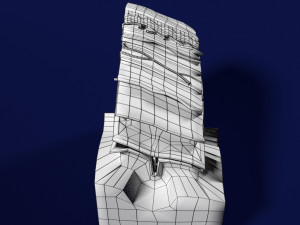

Brain with meninges scalp detailed labelled 3D 3D मॉडल

A blend model of brain along with its covering layers (meninges), skull bone and scalp labelled in detail and anatomically precise. The parts depicted are white, gray, pia, arachnoid, dura, bone, skin, fat, aponeurosis, periosteum, falx cerebri and more.

The material is high resolution image textures and normal maps based on non overlapping UVs. The texture and normal maps are packed with the blend file itself.